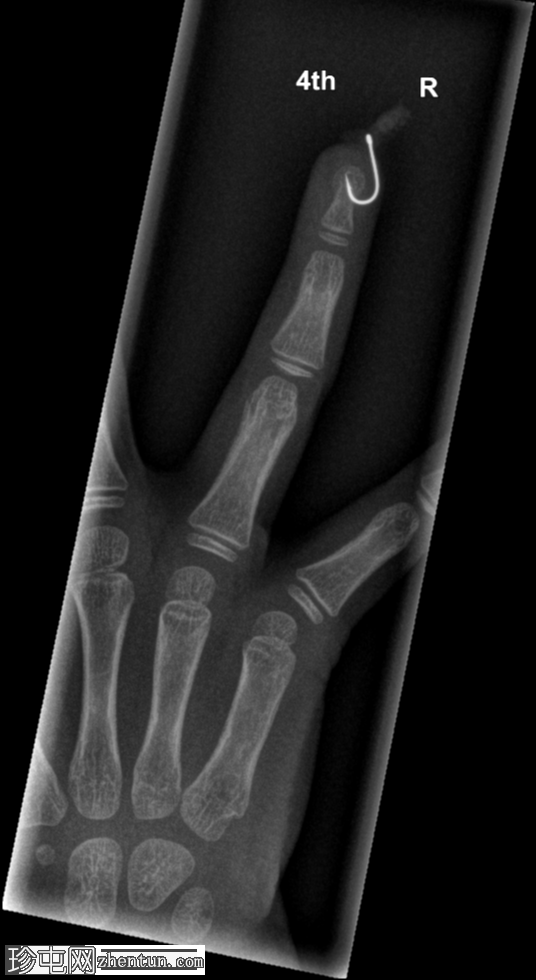

年龄:5岁

性别:男

右手无名指

X光片

正位片

鱼钩异物,附有蛆虫。

鱼钩异物较为常见,但像本例中鱼钩上还附着蛆虫的情况则较为罕见!